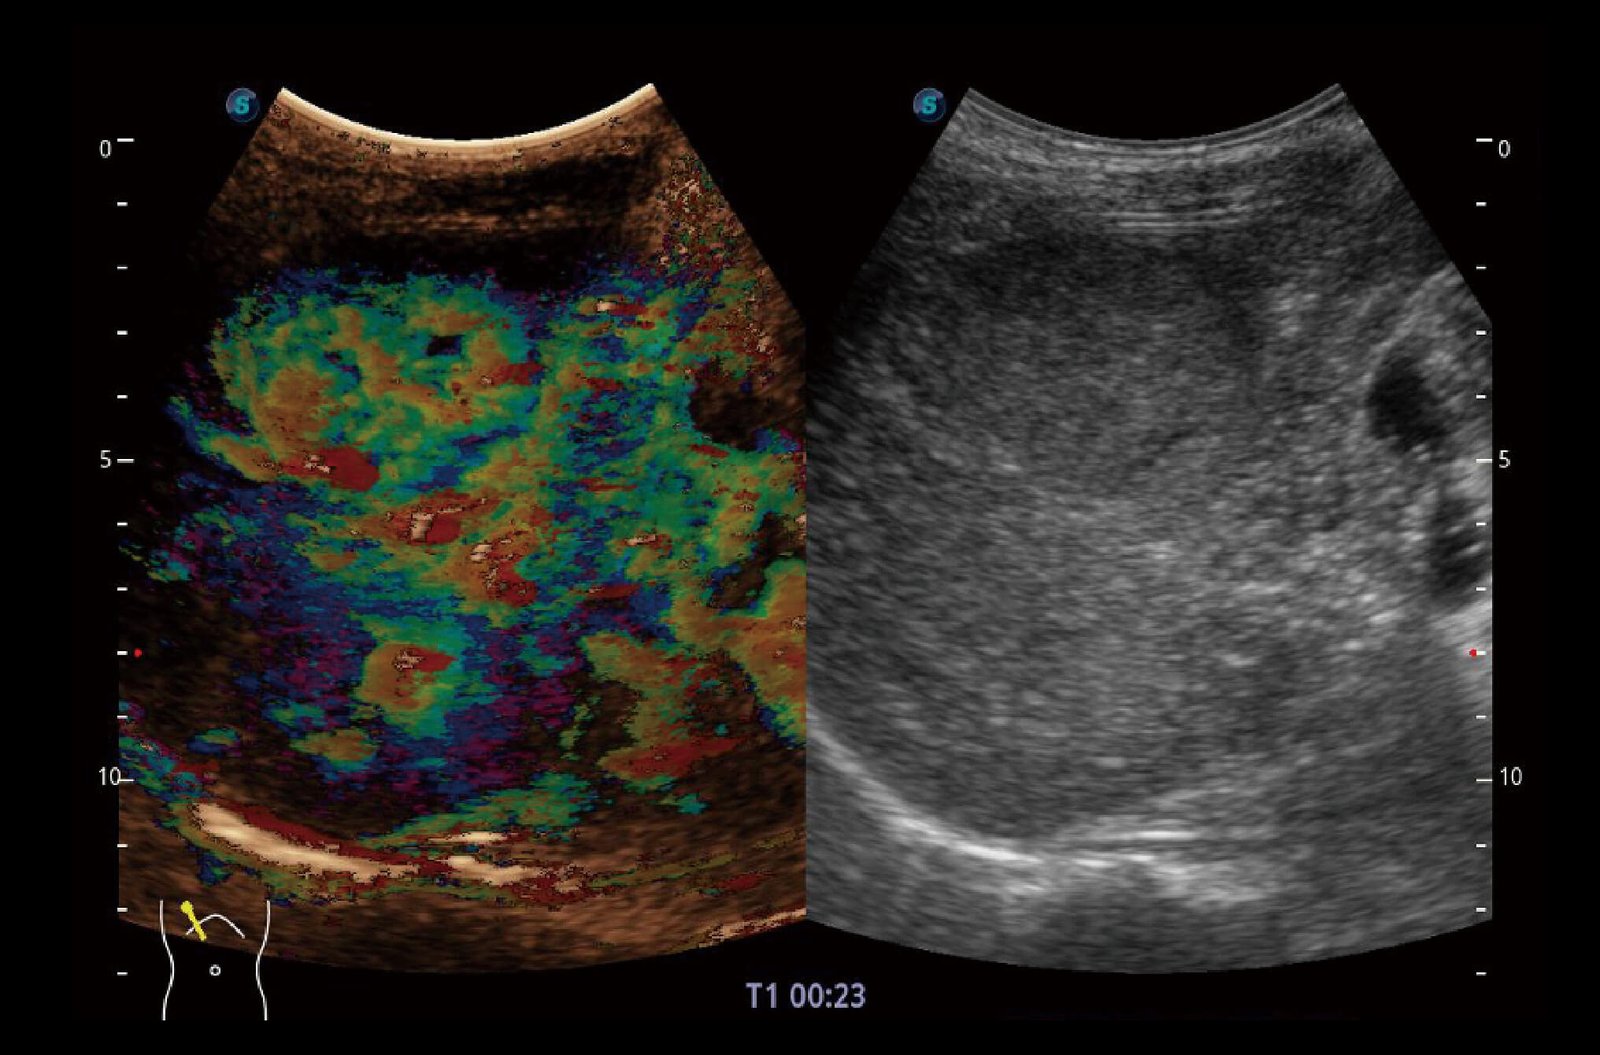

SR-Flow

Highly effective filter technology visualizes slow flows, enabling a vivid Doppler display with high sensitivity.

Micro F

Micro F provides an innovative method to expand the range of visible flow in ultrasound, especially for visualizing hemodynamic of tiny vessels.

Bright Flow

3D-like color Doppler flow strengthens boundary definition of vessel walls, without the need of using volume transducer.